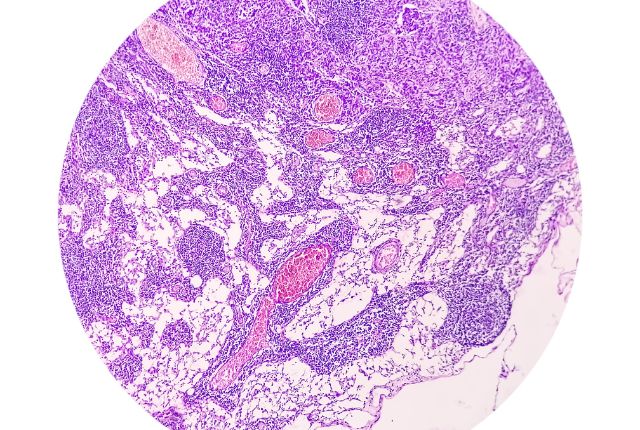

L'adénocarcinome est un type de cancer. Il s'agit d'une tumeur maligne qui se crée à partir d'un certain type de cellules, très répandues dans l'organisme : les cellules épithéliales glandulaires. L'épithélium est un tissu qui recouvre le corps et tapisse les organes dits creux : cela concerne, par exemple, l'appareil respiratoire, le système digestif, les organes reproducteurs et urinaires. Le cancer du sein, le cancer de l'estomac, le cancer de la prostate, le cancer du pancréas, le cancer colorectal sont souvent associés aux adénocarcinomes. L'adénocarcinome représente une forme spécifique de carcinome.